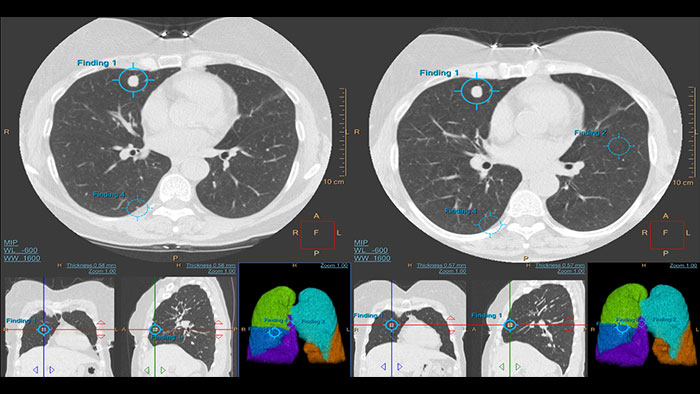

Lung Nodule Assessment (LNA)

CT Lung Nodule Assessment (LNA)

Assessing lung nodules over time

Enables review and analysis of thoracic CT images, providing segmentation, quantification and characterization of physician-indicated lung nodules. The application can be used in both diagnostic and screening evaluations, supporting Low Dose CT Lung Cancer Screening*

• Automatic lung and lobes segmentation and one click 2D and 3D nodule segmentation.

• Supports LungRADS categorization, Fleischner Society guidelines for incidental findings as well as a Risk Calculator tool**.

• Pre-filled data including characteristics for each nodule in configurable presets are provided automatically by the application.

• Lung and nodule segmentations can be shared as RT Structures.